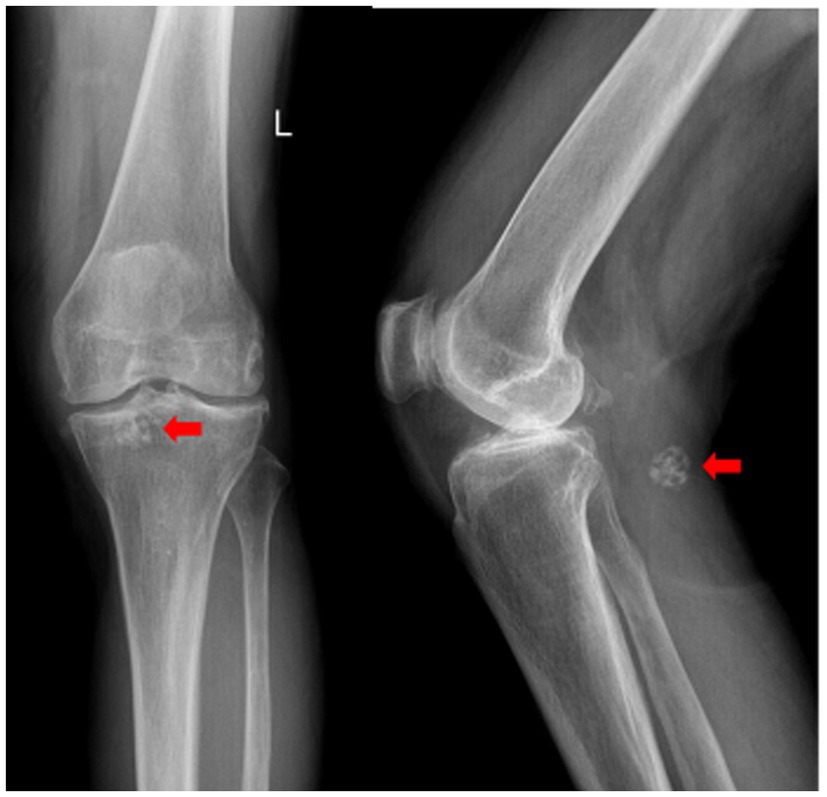

The imaging examination results revealed that the X-ray images demonstrated the presence of osteophyte shadows at the margins of the bones constituting the left knee joint, with osteophytes having formed in certain areas. Additionally, the tibial intercondylar eminence exhibited a pointed morphology, the joint space was significantly narrowed, and the subchondral bone displayed signs of sclerosis. In the popliteal region of the left knee, a spherical coral-like calcified nodular shadow approximately 16 mm in diameter was observed (Figure 1).

Figure 1. Anteroposterior and lateral radiographs of the left knee. Degenerative changes are evident. A spherical coral-like calcified nodule is indicated by the red arrow.

X-ray is a commonly used imaging method for diagnosing synovial chondromatosis. In lateral knee X-rays, notable calcification or ossified loose bodies can be observed, which is particularly important for diagnosing patients in Milgram stage III. In this study, the patient’s X-ray images exhibited calcified nodules resembling spherical coral. However, X-ray examinations have difficulty distinguishing synovial chondromatosis from other soft tissue tumors, and there is also uncertainty in diagnosing popliteal cysts. Therefore, further CT and MRI examinations are necessary. CT, through three-dimensional reconstruction, can clearly display the number, location, size, and morphological characteristics of loose bodies. For joint effusion and early knee joint lesions, MRI, with its superior soft tissue signal resolution, can effectively illustrate the degree of synovial hyperplasia, the size of popliteal cysts, and the morphology of intra-capsular loose bodies. These imaging findings provide precise data for determining the number and positional relationships of tumors, offering critical references for the complete intraoperative removal of lesions and reducing the postoperative recurrence rate (15).